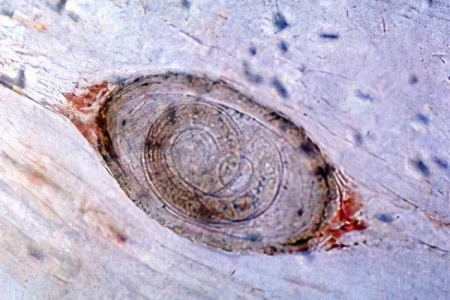

Исследование мяса больных животных

При многократном увеличении исследуется мясо животного, которое может быть источником заражения. С помощью микроскопа выявляются капсулы с личинками в тканях инфицированного животного.

Внешний вид мяса, заражённого трихинеллами, почти не отличается от мяса здоровых животных. Концентрация трихинелл в поражённых тканях может достигать 200 особей на 1 грамм. Исследование мяса проводится в лабораторных условиях с использованием микроскопа. По завершении анализа на тушу наносится специальное клеймо.